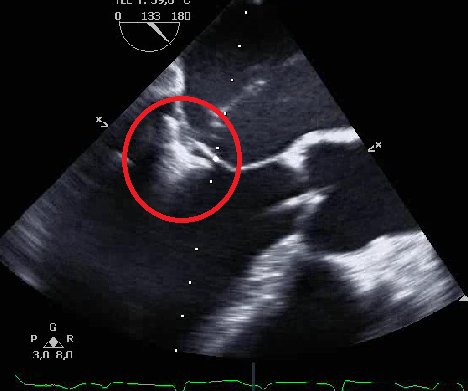

Auf den Bildern sehen Sie eine Echokardiografie vor (01), während (02) und nach (03) einer kathetergestützten Rekonstruktion der Mitralklappe mittels MitraClip®. Der große Pfeil zeigt eine ausgeprägte Undichtigkeit vor dem Eingriff (01). Der rote Kreis markiert die MitraClip-Implantation (02). Und der kleiner Pfeil verdeutlicht eine nur noch geringe Undichtigkeit nach dem Eingriff (03).